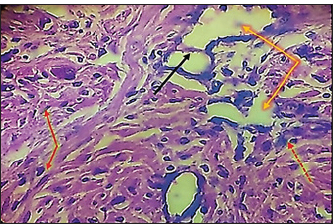

Fig. 7. Histopathological section of testes from a dog in the zinc gluconate group at 30 days post-intrasticular injection, showing exfoliation of germ cells (red arrows), infiltration of inflammatory cells (white arrows), Leydig cell clusters (yellow arrow), edema (star), and congestion (yellow head arrow) (H & E stain 10X). Surgical groupIn the surgical group (GII), the main characteristic findings at 30 days post-surgery were degeneration of seminiferous tubules, multinucleated spermatid, infiltration of inflammatory cells, atrophy of Leydig cells, and vacuole degeneration of basal and Sertoli epithelium (Fig. 8). Furthermore, there was loss of the straight shape of the tubuli recti, disequimentaion of the tubuli recti epithelium, and proliferation of myoid cells (Fig. 9). Other sections showed coagulative necrosis and ghost tubules in the rete testis (Figs. 10 and 11).

Fig. 10. Histopathological section of testes from a dog in the surgical group at 30 days post-surgery, showing coagulative necrosis (red arrow), ghost tubules in the rete testis (red dotted arrow), and infiltration of inflammatory cells (red head arrow) (H & E stain 10X).

Fig. 11. Histopathological section of testes from a dog in the surgical group at 30 days post-surgery, showing tunica albuginea thickening (white arrows with two heads), inflammatory cell infiltration (yellow arrow), and vacuolar degeneration (red dotted arrow) (hematoxylin and eosin stain 4X). Control groupIn the control group, the histopathological testicular section expresses interstitial septa that surround the seminiferous tubules and contain Leydig cells. Various stages of spermatogenesis and Sertoli cells were also recognized (Fig. 12).